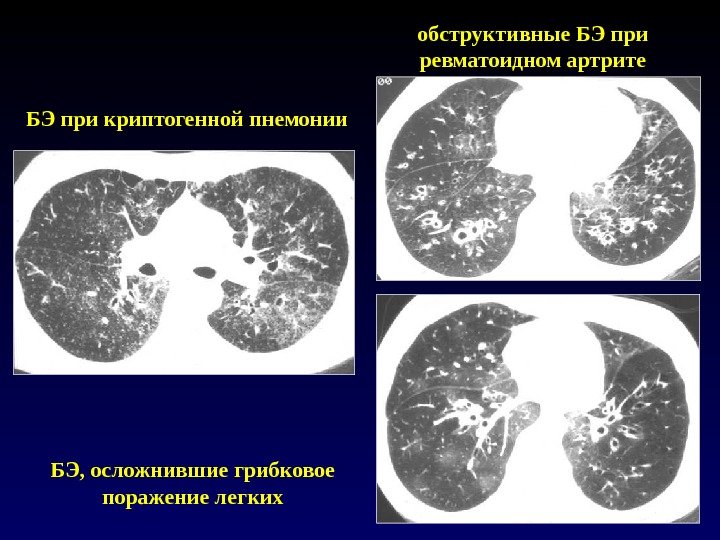

обструктивные БЭ при ревматоидном артрите БЭ при криптогенной пнемонии БЭ, осложнившие грибковое поражение легких обструктивные БЭ при ревматоидном артрите БЭ при криптогенной пнемонии БЭ, осложнившие грибковое поражение легких